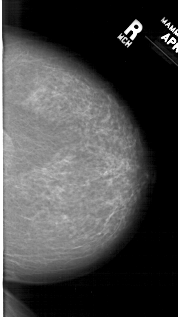

A_1307_1.LEFT_CC

LEFT_CC LINES 6871 PIXELS_PER_LINE 4006 BITS_PER_PIXEL 12 RESOLUTION 43.5 OVERLAY